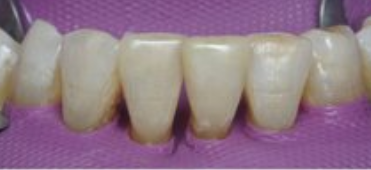

FICHE CLINIQUE Prothèse fixée conventionnelle : Couronnes et bridges